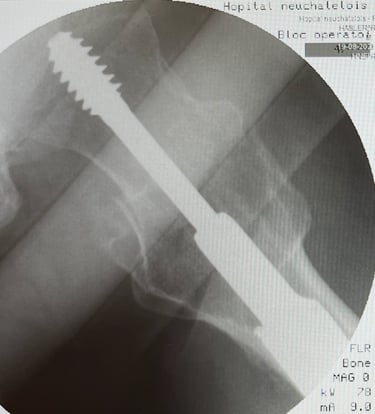

Diagnosi e trattamento delle patologie dell’anca, incluse artrosi, tendinopatie e traumi.

Terapie conservative, infiltrative e chirurgiche, inclusa chirurgia protesica d’anca.